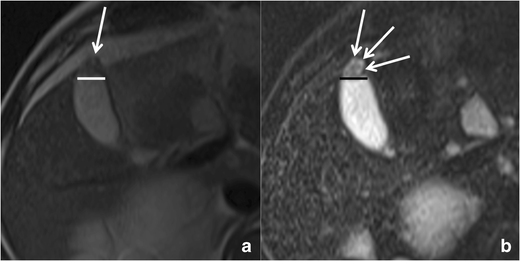

RAS typically appear markedly hyperintense on T2-weighted images (Fig. 10) [29], hypointense on T1-weighted images and show no contrast enhancement. Anyway, progressive bile concentration and calcification development may change the MRI appearance of RAS that may become increasingly hyperintense on T1-weighted images (Fig. 11) and relatively hypointense on T2-weighted ones.

Fig. 10

Gallbladder adenomyomatosis: typical MRI findings. On MRI, GA can be identified as a mural thickening (line) containing small T2-hyperintense spaces representing RAS (arrows). RAS can be better identified on fat-saturated T2-weighted images (b) than on non-fat-saturated ones (a)

Bild vergrößern

Fig. 11

MRI of gallbladder adenomyomatosis: T1-hyperintense Rokitansky–Aschoff sinuses. Rokitansky–Aschoff sinuses (arrow) may appear hyperintense on T1-weighted images if containing concentrated bile or calcifications